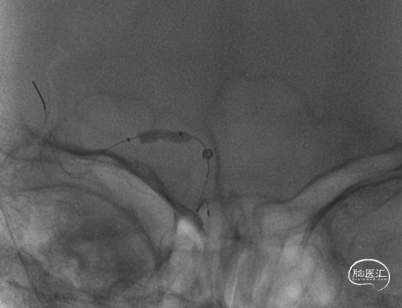

SacSpeed®球囊扩张导管 2.0*9mm球囊到位过程。

SacSpeed®球囊扩张导管 2.0*9mm球囊到位造影:血管再闭塞。

SacSpeed®球囊扩张导管缓慢扩张过程中见明显腰线。

球扩后造影:狭窄明显改善,前向血流明显好转,未见血栓征象,球囊部分回收支架,撤出。